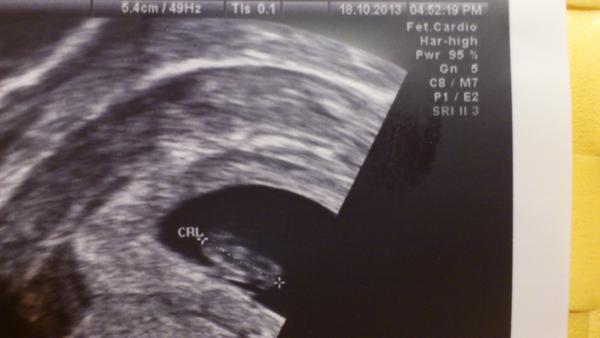

Tak jsem fakt těhule! Srdíčko krsně blikalo a dostala jsem už rovnou průkajdu. Mimi odpovídá 7+1 a měří 10,12 mm. 😎